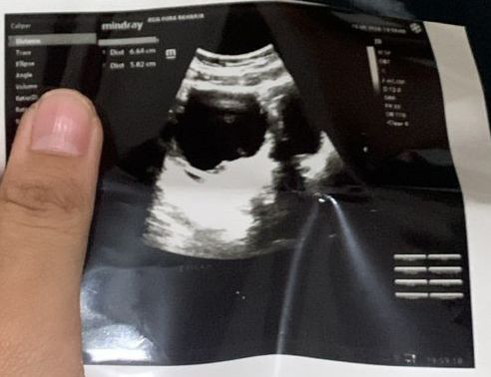

moms kira kira kandunganku baru 5weeks usg pertama katanya belum keliatan kantong malah keliatan kista. tapi dokternya sendiri ragu sama pendapatnya kalo itu kista. ada yang bisa baca hasil usg ga ya mom itu kista atau bukan?π© panik banget.